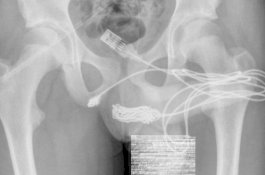

Iseng Ukur Kejantanan, Kabel USB yang Kusut Bersarang dalam Uretra Remaja 15 Tahun